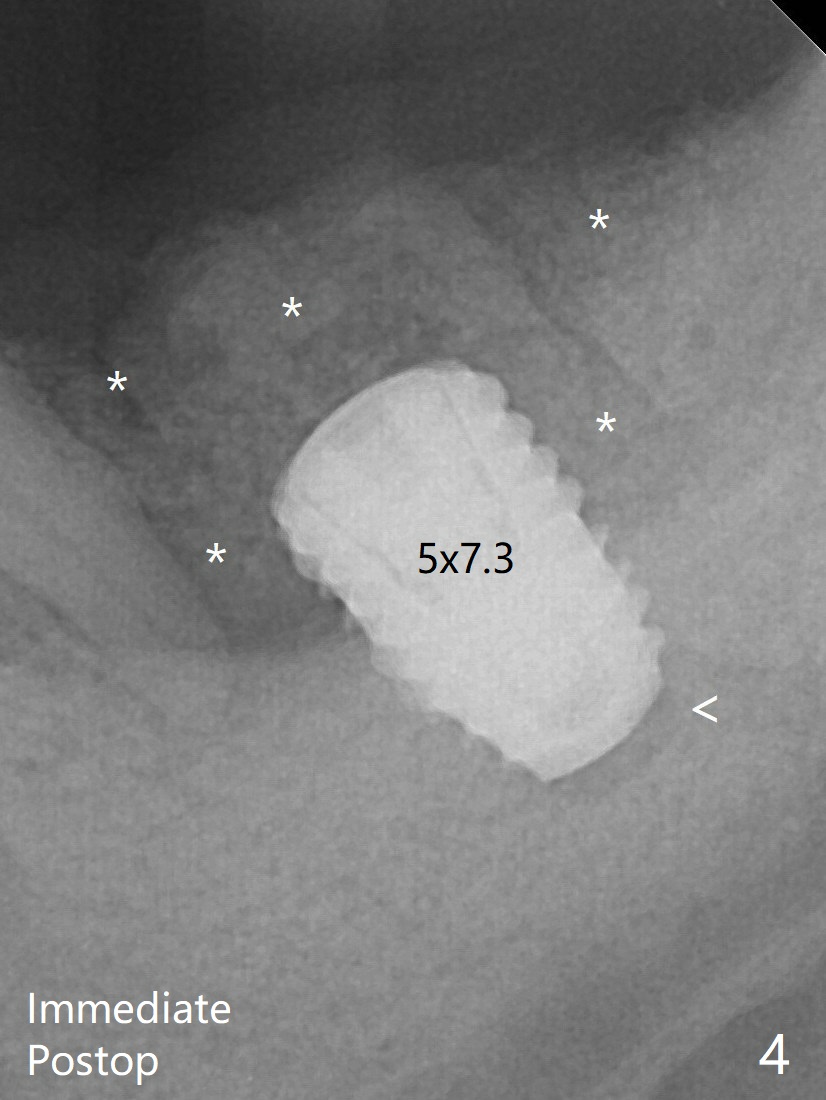

After implant removal, a 4.5x11.5 mm drill is used, but it cannot reach the depth due to high bone density. 800 RPM instead of 50 RPM may help. When the implant is reseated, it appears to be .5 mm deeper than before clinically, although it looks incompletely seated in X-ray (Fig.4 <). The insertion torque is 60 Ncm. Allograft mixed with PRF is placed around the implant with cover screw, particularly mesiolinguodistal (Fig.4 *). The majority of the bone graft is lost without immediate provisional in 4 months (Fig.9 * (<: socket shield)). Then a 5.5x5 mm healing abutment is inserted for impression next appointment.